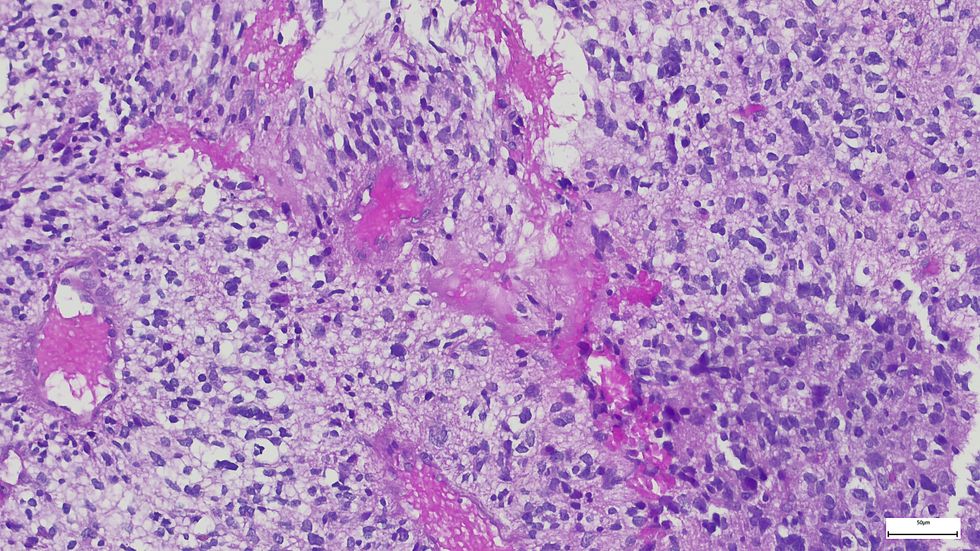

The dentist warned that any lesion appearing white, red or irregular, particularly if it's only on one side of the mouth, needs professional attention.

"If there is a lesion that looks white, red, irregular or on one side of the mouth, have a professional take a look, call a dentist," she urged viewers.

Lesions in the mouth could be a sign of cancer